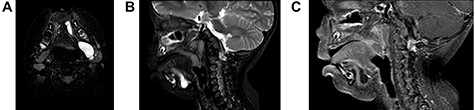

(A) On axial view, MRI demonstrated multi-lobulated cystic mass, which showed hypersignal intensity on T2 weighted image involving left sublingual, submandibular, pharyngeal and parapharyngeal spaces; (B) On sagittal view, MRI demonstrated multi-lobulated cystic mass, which showed hypersignal intensity on T2 weighted image involving left sublingual and submandibular spaces; (C) On sagittal view, MRI demonstrated multi-lobulated cystic mass, which showed hyposignal intensity on T1 fat suppression with gadolinium involving left sublingual and submandibular spaces.

A 2-year-old boy presented with a slow growing mass under the tongue for 6 months. He was born without any anomaly. The development status was within average except delay speech due to the mass at floor of mouth. The physical examination revealed left sublingual cystic lesion measuring 1.0 × 1.0 cm. Ankyloglossia was found (Fig. 1). Cervical lymph nodes could not be palpated. Magnetic resonance imaging (MRI) demonstrated multi-lobulated cystic mass, size about 3.15 × 2.1 × 2.9 cm, which showed hypersignal intensity on T2 weighted image, hyposignal intensity on T1 weighted image, T1 fat suppression, T1 fat suppression with gadolinium involving left sublingual, submandibular, pharyngeal and parapharyngeal spaces (Fig. 2A–C). The provisional diagnosis was lymphatic or venous malformation.

MRI demonstrated multi-lobulated cystic mass, which showed hypersignal intensity on T2 weighted image, hyposignal intensity on T1 weighted image. Contrast to some literature that MRI revealed a homogeneous, unilocular cystic lesion with hypersignal intensity on T2 and hyposignal intensity on T1 with contrast enhancement after gadolinium infusion [7]. According to the imaging feature demonstrate likely lymphatic malformation, although final diagnosis was a cyst lined by respiratory and squamous epithelium or BC.